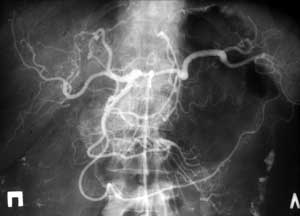

Рис. 3. Селективная целиакография. Стеноз чревного ствола, селезеночной артерии. Постстенотическое расширение общей печеночной артерии. Атеросклеротическое поражение.